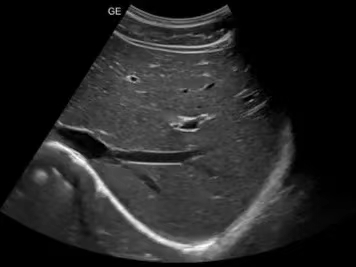

高清病例展示图:

ct什么牌子的好【喜讯】瑶医医院影像科大型CT设备顺利开机并投入使用_https://www.jmylbn.com_新闻资讯_第14张

◆ 肝脏图像 ◆